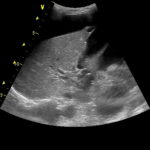

Найбільш ефективними вважаються такі методи, які будуть наведені нижче. Наприклад, УЗД черевної порожнини. Це дає можливість оглянути докторові особливості деяких органів і визначити їх стан.

Таким чином може бути обстежена система проток жовчі, жовчний міхур і печінка. Також цим способом досліджується і підшлункова зі своєю системою проток.

Підшлункова теж має зв’язок з системою проток жовчі в організмі. При використанні УЗД лікар може візуально визначити аномалії в цих органах, поява різних утворень, а також жовчних конкрементів.